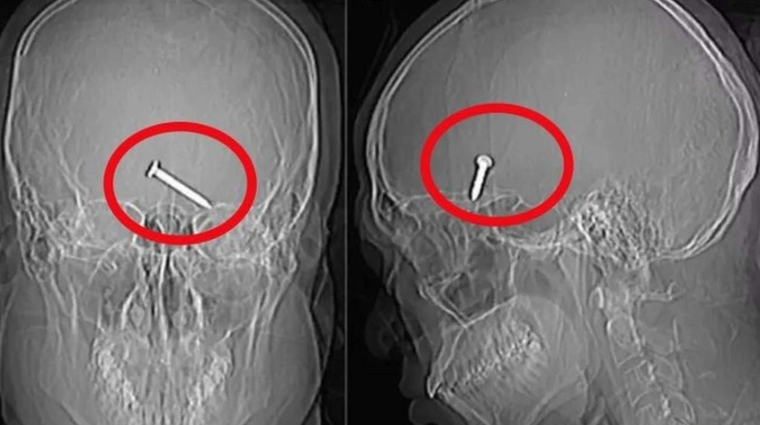

Dəhşətli iş qəzası! Gözündən girdi, beynindən çıxdı!

Dəhşətli iş qəzası! Gözündən girdi, beynindən çıxdı!Malayziyada tikitinti aparılan ərazidə baş verən iş qəzası qorxulu anlar yaşadıb.

Sonxeber.az xarici mənbəyə istinadən xəbər verir ki, tikintidə qoruyucu eynək taxmadan işləyən 30 yaşlı inşaat işçisi üzünü mismar vuran maşına yaxınlaşdıran zaman gözünə mismar girib.

Mismar maşınının qəfil işləməsi nəticəsində sol gözünə 3 sm qalınlığında mismar ilişən işçi təcili olaraq xəstəxanaya çatdırılıb və əməliyyat olunub.

Müayinələr nəticəsində mismarın beyninə batıb. Xəstə möcüzəvi şəkildə sağ qalıb və görmə qabiliyyətini itirməyib.